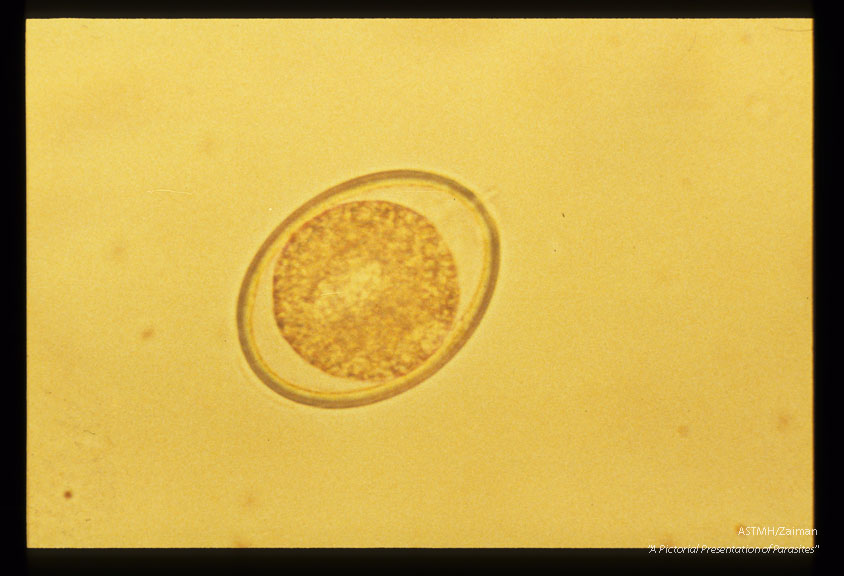

Development and hatching of larva.

Ascaris

Description: Development and hatching of larva.